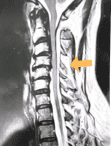

Case Studies